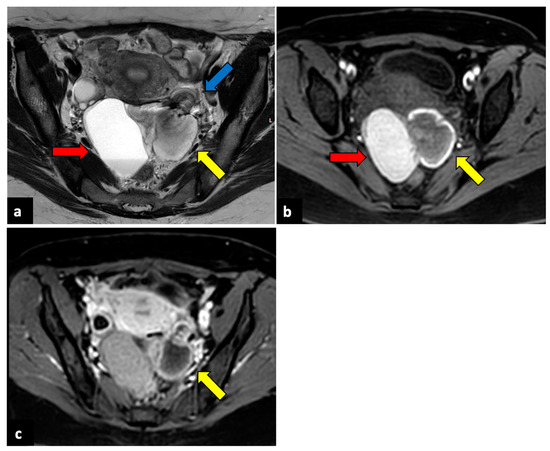

Utility of the Diffusion Weighted Sequence in Gynecological Imaging: Review Article

by Apurva Bonde, Eduardo Andreazza Dal Lago, Bryan Foster, Sanaz Javadi, Sarah Palmquist and Priya Bhosale

Functional imaging with diffusion-weighted imaging (DWI) is a complementary tool to conventional diagnostic magnetic resonance imaging sequences. It is being increasingly investigated to predict tumor response and assess tumor recurrence. We elucidate the specific technical modifications of DWI preferred for gynecological imaging, including [...] Read more.

Functional imaging with diffusion-weighted imaging (DWI) is a complementary tool to conventional diagnostic magnetic resonance imaging sequences. It is being increasingly investigated to predict tumor response and assess tumor recurrence. We elucidate the specific technical modifications of DWI preferred for gynecological imaging, including the different b-values and planes for image acquisition. Additionally, we discuss the problems and potential pitfalls encountered during DWI interpretation and ways to overcome them. DWI has a wide range of clinical applications in malignant and non-malignant gynecological conditions. It provides supplemental information helpful in diagnosing and managing tubo-ovarian abscess, uterine fibroids, endometriosis, adnexal torsion, and dermoid. Similarly, DWI has diverse applications in gynecological oncology in diagnosis, staging, detection of recurrent disease, and tumor response assessment. Quantitative evaluation with apparent diffusion coefficient (ADC) measurement is being increasingly evaluated for correlation with various tumor parameters in managing gynecological malignancies aiding in preoperative treatment planning. Newer advanced DWI techniques of diffusion tensor imaging (DTI) and whole body DWI with background suppression (DWIBS) and their potential uses in pelvic nerve mapping, preoperative planning, and fertility-preserving surgeries are briefly discussed. Full article

Show Figures

Figure 1